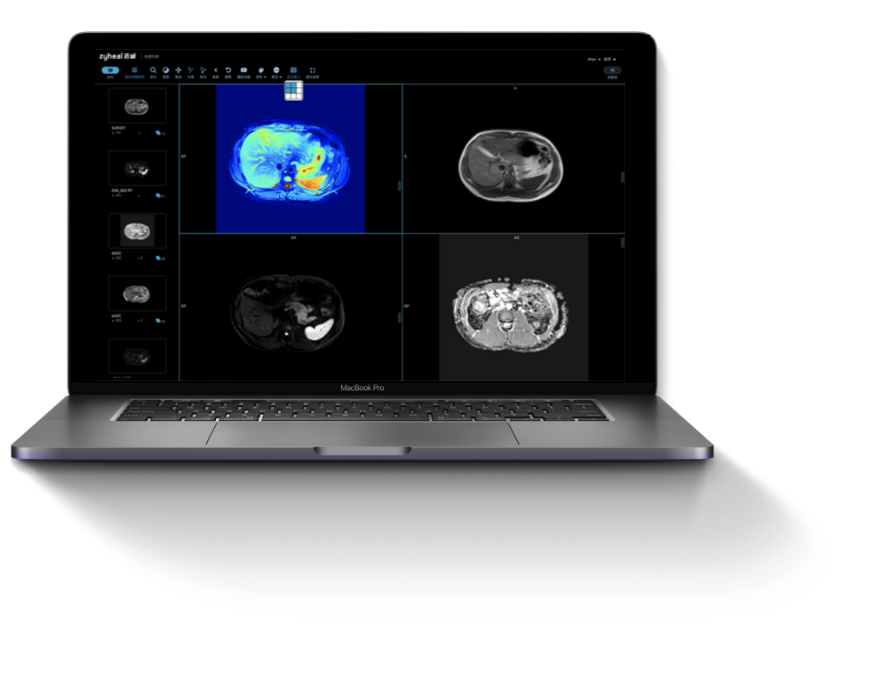

志御科技致力于成為全球肝

腦醫療AI領域的創新引領者

上海志御軟件信息有限公司(簡稱:志御科技)是中國領先的高科技醫療AI創新企業,創始團隊由知名醫學影像科學家隊伍及世界500強企業資深管理和營銷精英組成。公司致力于成為全球肝、腦醫學影像AI分析、AI輔助診斷以及AI遠程醫療的創新引領者,打造肝、腦醫療AI第一品牌。

閱讀更多